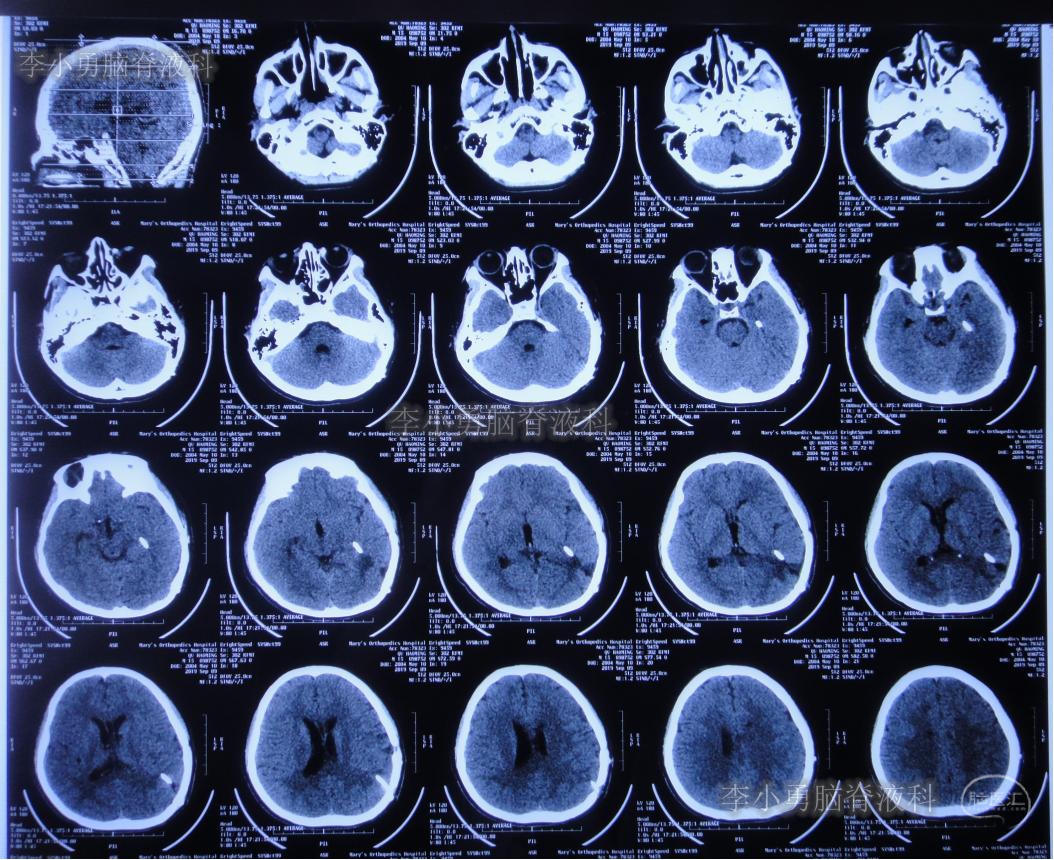

次日2019年4月3日(脑出血后8天),转至河南省郑州市某三甲医院;入院当日头颅CT(图-5)及CTA(图-6)检查结果:出血量较昨日无增加,动脉血管未见明显异常。

图-5:2019年4月3日头颅CT:出血量无增加

图-6:2019年4月3日头颅CTA:未见明显异常

继续给予脑室外引流1周后即2019年4月11日,再次复查头颅CT(图-7):脑室内积血明显减少,脑室不大。

图-7:2019年4月11日头颅CT:脑室内积血明显减少

为防止动脉瘤破裂,停止了每日的腰椎穿刺治疗,并积极完善动脉瘤夹闭术前准备。拔除第二次脑室外引流管后12天即2019年4月23日,患者出现哭闹、呕吐、发热及烦躁症状,紧急检查头颅CT(图-8):脑室较前略扩大,未见明显积血。

图-8:2019年4月23日头颅CT:脑室略扩大